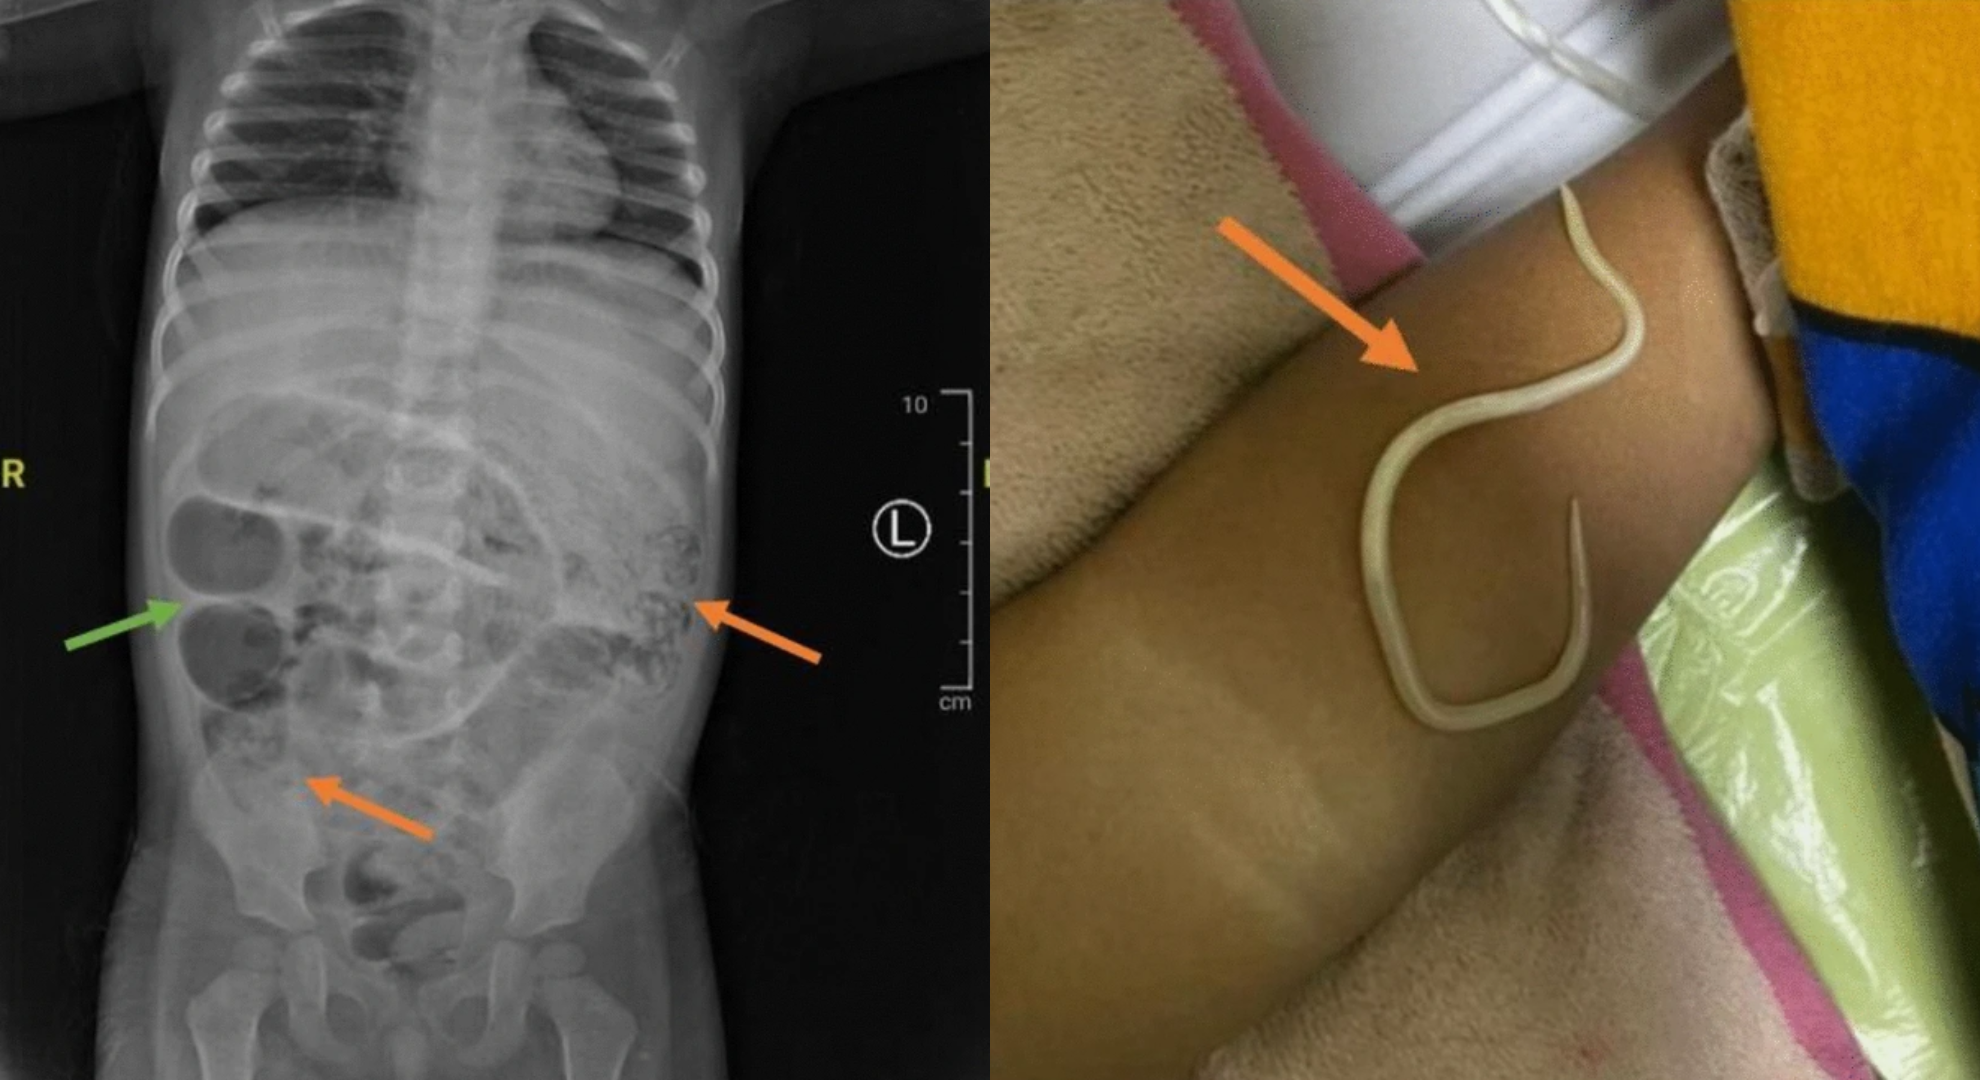

▲印尼3歲男童便祕3天發燒,就醫檢查驚覺體內有大量蛔蟲。(圖/翻攝自Journal of Medical Case Report)

根據外媒《Daily Mail》報導,這起個案於4月10日刊登在《Journal of Medical Case Report》,一名3歲男童腹脹3天沒有排便,後來甚至出現發燒症狀,嚇得父母急忙帶他去醫院接受治療。起初醫師診斷男童只是便秘,怎料住院隔天男童竟在嘔吐過程中吐出蟲,院方趕緊幫他照胃部X光,結果發現體內狀況異常,並決定動手術。

醫療團隊在手術過程中,發現大量蛔蟲阻塞小腸3處不同區域,他們在小腸切開一個小口,透過輕輕擠壓的方式,將蛔蟲擠出後,再把傷口縫合,並將蛔蟲送檢。術後,醫師開藥讓男童服用,男童也順利在一周後出院,並持續服藥。至於男童體內為何會有如此多的蛔蟲?醫療人員推測,男童可能因飲用受污染的水或赤腳行走接觸寄生蟲而感染。他們警告,若未能及時接受治療,病情可能進一步惡化,最終導致腸穿孔,甚至危及生命。